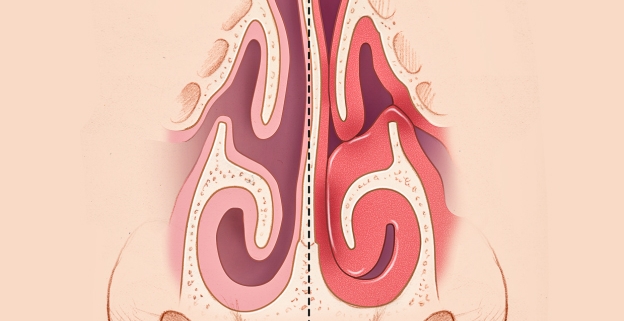

برای درک بهتر مشکل، ابتدا باید بدانیم [شاخک بینی چیست؟ نقش شاخکهای تحتانی در تنفس](لینک به مقاله اول) بسیار حیاتی است. شاخکها با گرم و مرطوب کردن هوا، نقش فیلتر را ایفا میکنند. اما زمانی که بافت آنها بیش از حد متورم شود، مسیر تنفس را مسدود میکند.

انحراف یا شاخک؟

بسیاری از بیماران با فرض انحراف بینی مراجعه میکنند. برای تمایز این دو، پیشنهاد میکنم مقاله [تفاوت انحراف بینی و بزرگی شاخک؛ کدام عامل گرفتگی شماست؟] را مطالعه کنید تا با روشهای تشخیصی فوقتخصصی ما آشنا شوید.